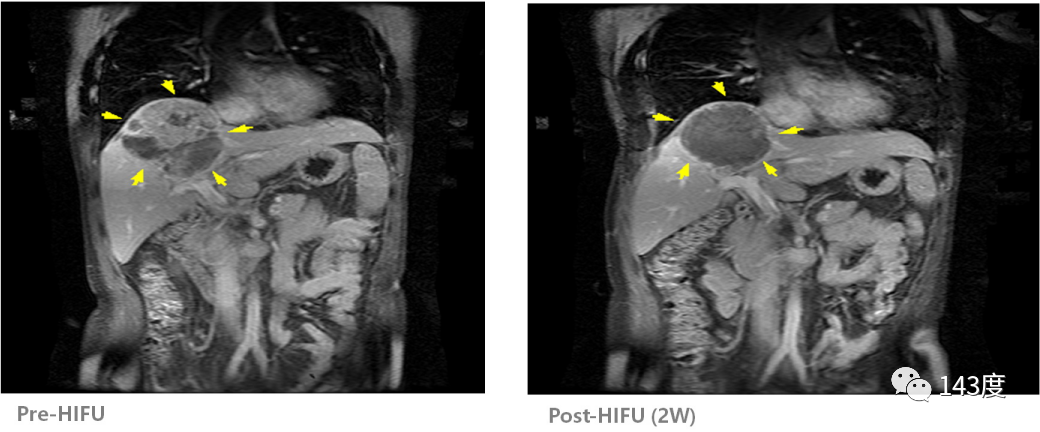

Liver Cancer Treatment Case 3:

Primary liver cancer

Follow-up after two weeks of HIFU treatment showed complete disappearance of the tumor!